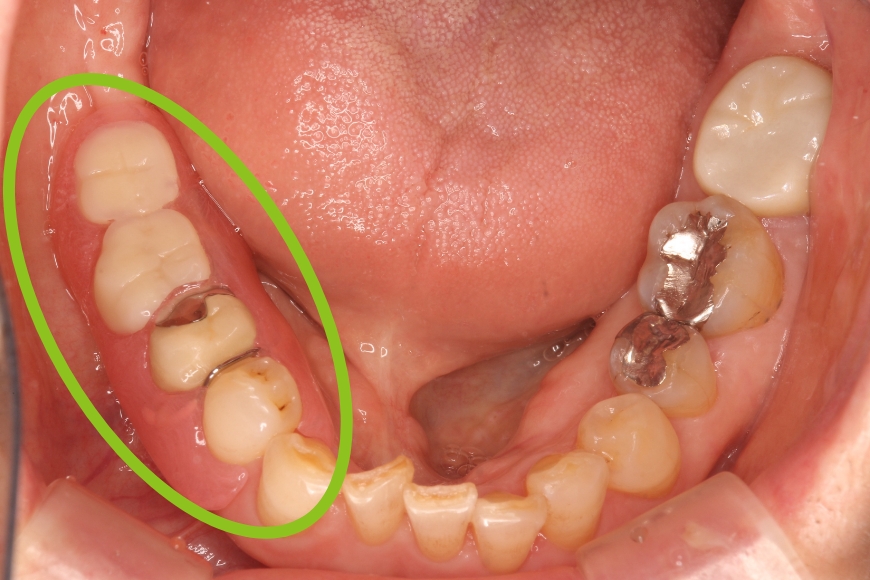

50代男性 左下の奥歯へのインプラント治療

治療内容 左下の奥歯が無く、食事がうまくできないことを主訴に来院されました。

歯が無い箇所にインプラント治療を行うことで、奥歯でしっかりと噛めるようになり、食事がおいしくなったとのことです。

治療期間・回数 治療期間:約3ヶ月

通院回数:5回程度

治療費用(総額)

440,000